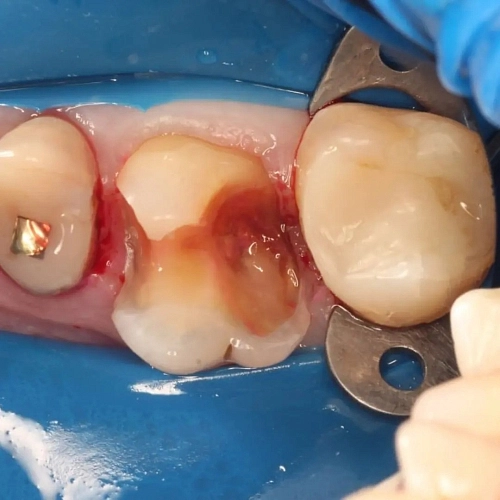

На фотографии представлена работа врача стоматолога Морозовой Александры Сергеевны, где зуб успешно подготовлен к дальнейшему протезированию.